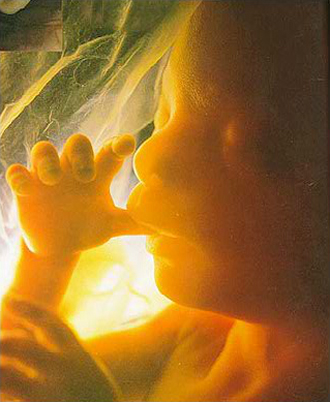

- 10주 이전

- 질 초음파 (1회/2주)

- 산모종합검사 (풍진, 간염, 매독, 에이즈, 빈혈, 혈액형, 갑상선, 소변검사)

- 10주 이후

- 초기 정밀 초음파

- 복부 초음파